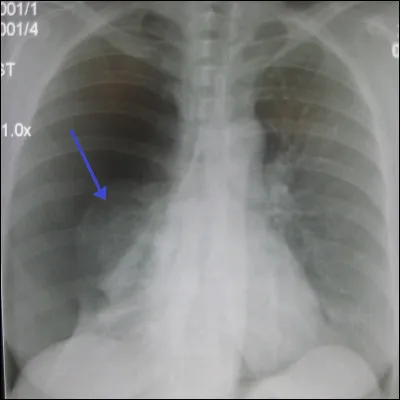

On ne peut pas parler d'imagerie médicale sans aborder les rayons X, qui sont utilisés par exemple dans la radiographie ou le scanner, pour ne citer qu'eux. Je vous ai mis ci-contre une radiographie pulmonaire, saurez-vous trouver le bon diagnostic ?